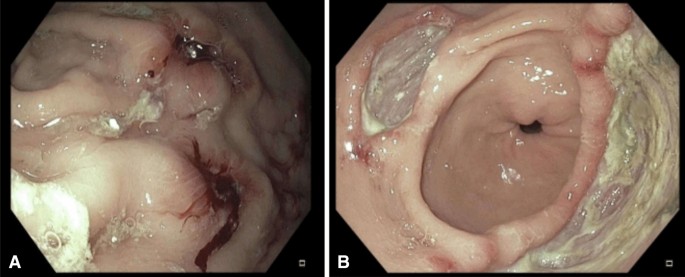

GFS: GERD LA-A moderate diffuse CAG c IM GU (A2) (about 40 * 30mm), r/o benign ulcer at LB/LC-PW -> bx (A) *4 (궤양의 변연에서 bx 시행함), clo was done. antral deformity 관찰됨. dumodenum: DU(S2) Catalyst endoscope inspection, and the result of the background esophageal inflammation.And the large stomach ulcer was found in the size of 40 x 30 mm. In the A2 stage, the shape of stomach ulcer was suspected of gastric ulcer.(positive= bacteri) The organization inspection is not a cancer, and the CLOtest for a helicopter bacteria.The results of tissue inspection was as follows.

As a result of gastric endoscope tissue inspection, the helicopter bacteria-positive stomach ulcer.I have been treated with stomach ulcer treatment, helicopter bacteria treatment, and helicopters were performed after three months later.If the stomach ulcer, you must receive stomach endoscope after appropriate treatment. For more information about gastric cancer. (of) and more information about the reasons for the details of the stomach) and see the following topics.